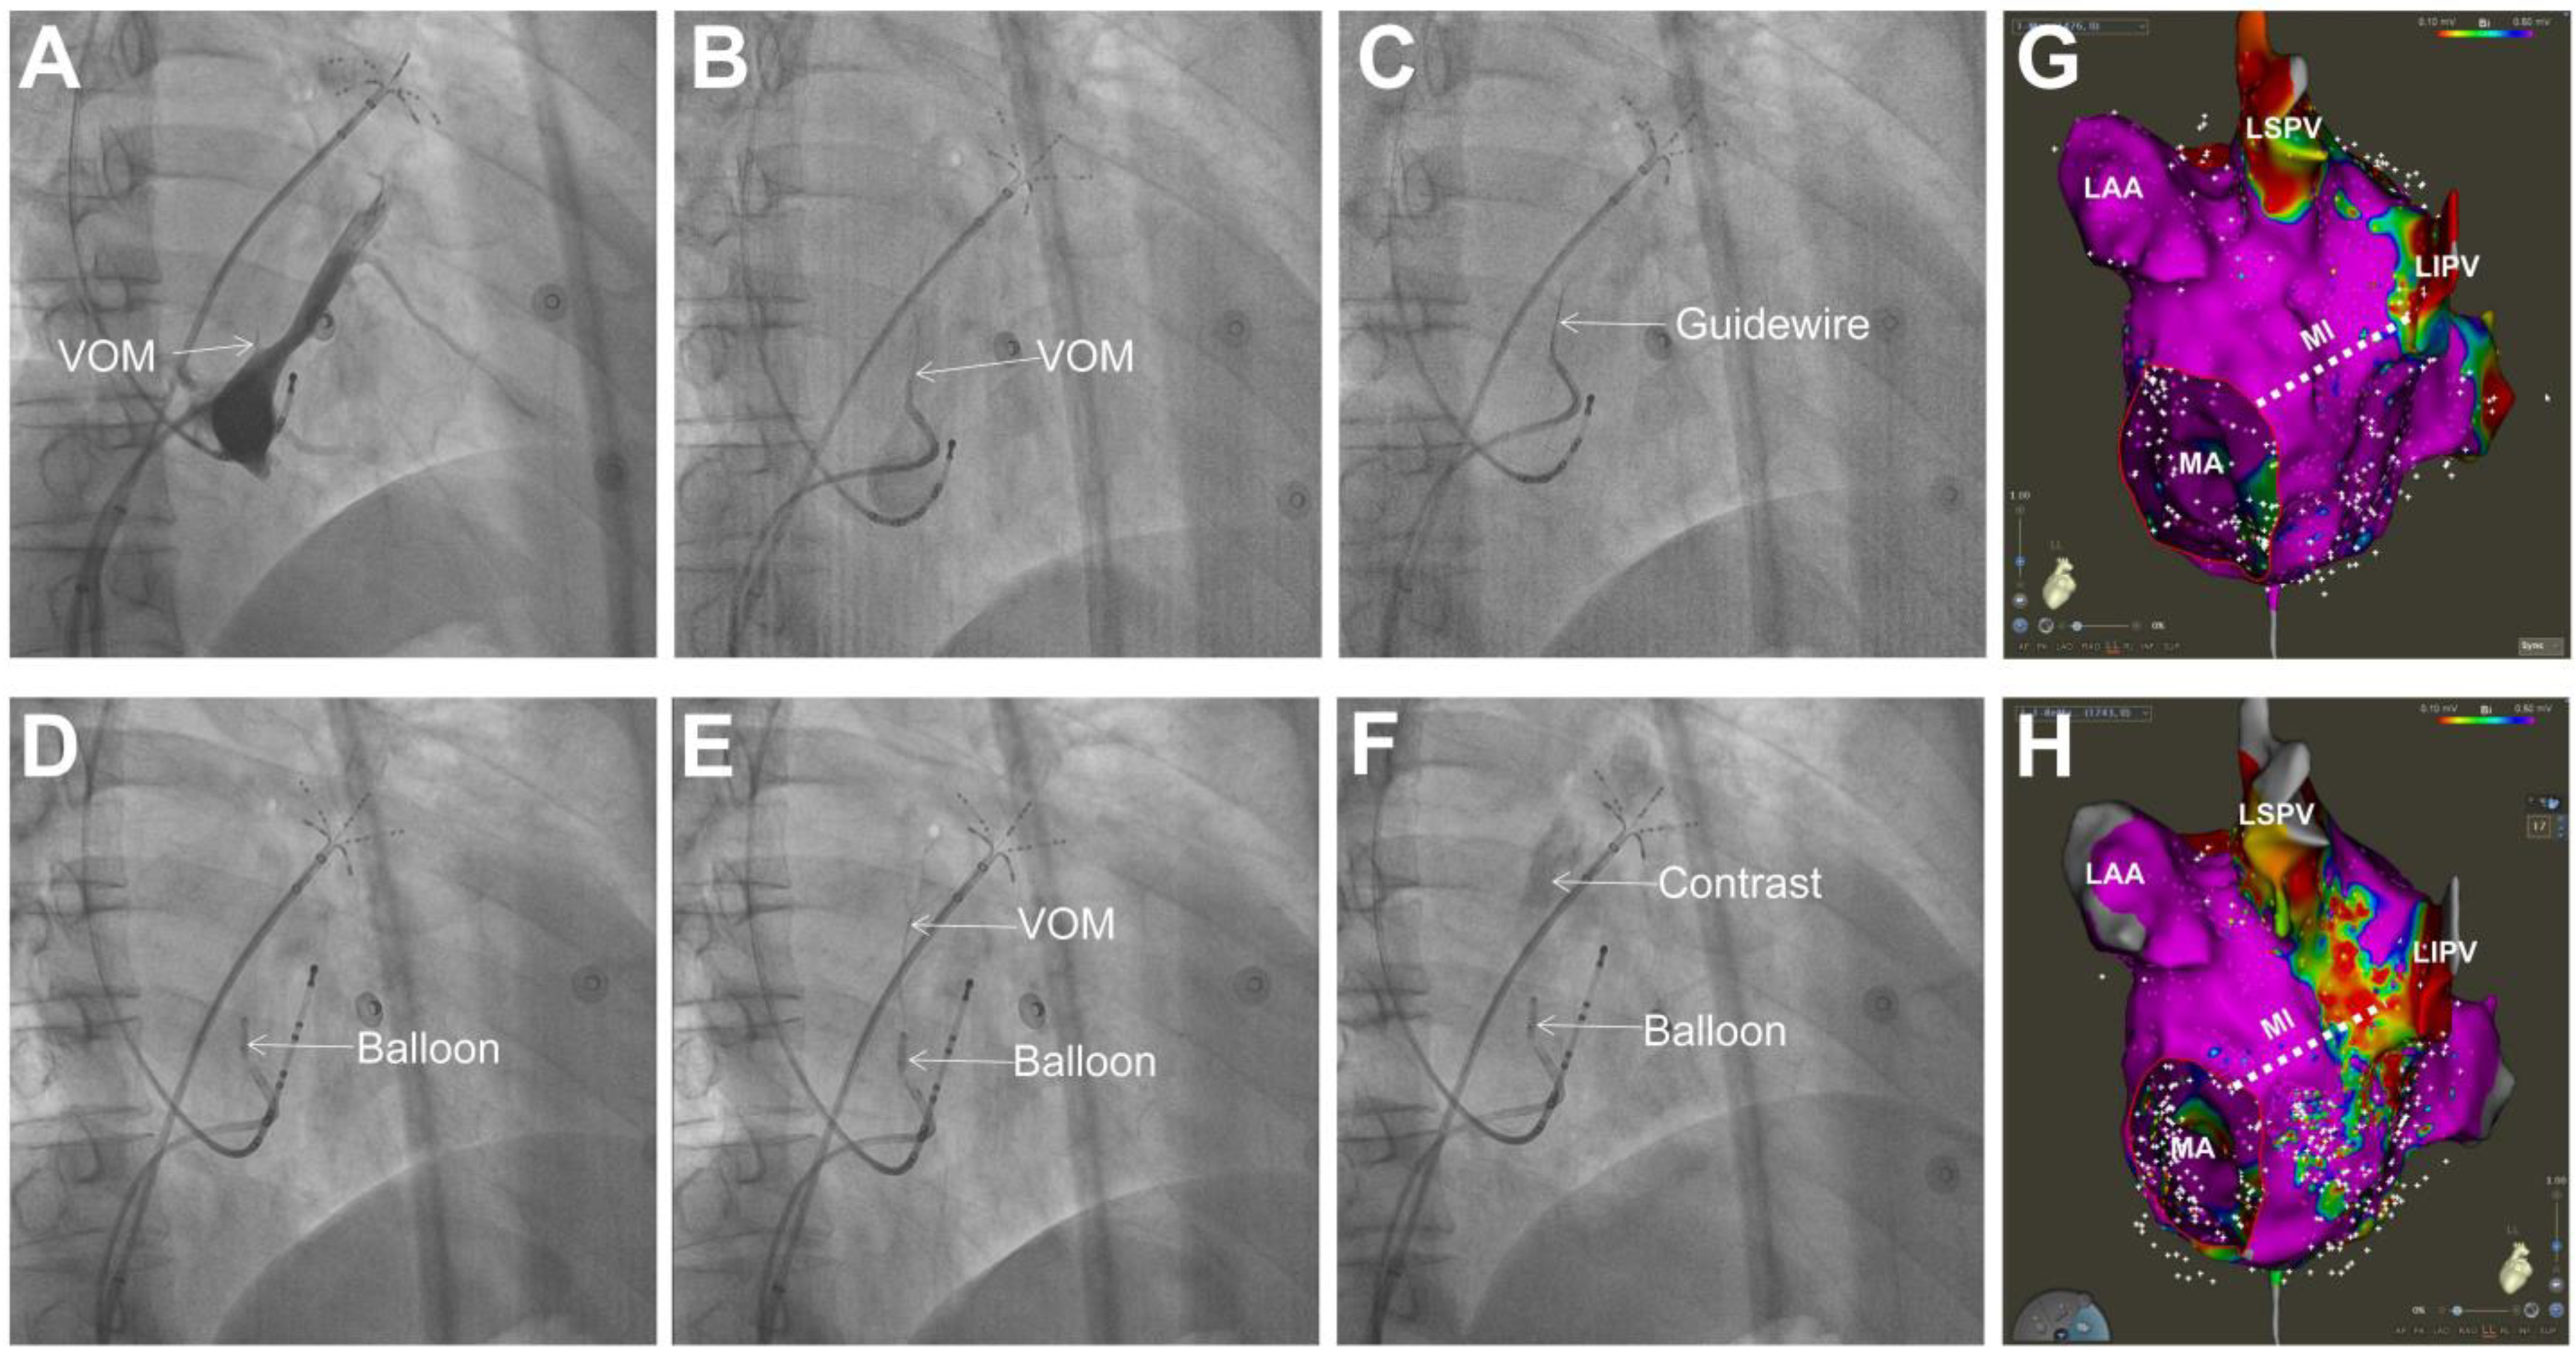

| Reference | Study Type | Study Population | Ablation Strategy | Primary Endpoint | N | Total Procedure Time (min) | Follow-Up Duration | Complications | Key Findings | ||

|---|---|---|---|---|---|---|---|---|---|---|---|

| EIVOM | Control | EIVOM | Control | ||||||||

| Pambrun et al. 2019 [44] | Single-arm | Persistent AF | EIVOM + PVI + MI line + Roof line + CTI | - | Freedom from arrhythmia recurrence | 10 | - | 270 ± 29.9 | 6 m | None | AF termination and noninducibility were achieved in 50% and 90% of the patients, respectively. All patients were free from arrhythmia recurrence during follow-up. |

| Liu et al. 2019 [39] | Retrospective, observational | Non-paroxysmal AF | PVI + substrate modification + EIVOM | PVI + substrate modification or PVI | A recurrence of AF or any atrial arrhythmia | 32 | 64 and 32 | 125.4 ± 65.6 vs. 149.7 ± 45.9 vs. 113.4 ± 52.1 | 3.9 ± 0.5 y | - | Total atrial arrhythmia recurrence was 28.1%, 59.7%, and 44.6%, respectively. Left atrial diameter >45 mm and hypertension were independent risk factors for recurrence. |

| Valderrábano et al. 2020 [40] | Multi-center randomized controlled trial | Persistent AF | Catheter ablation (sequential approach) + EIVOM | Catheter ablation alone | Freedom from AF or AT after a single procedure, without AADs, at both 6 and 12 months | 185 | 158 | 215.9 ± 77.7 vs. 190.3 ± 63.5 | 6 m and 12 m | 34/185 vs. 27/158 | Freedom from AF or tachycardia was 49.2% (91/185) vs. 38% (60/158) at 6 and 12 months after a single procedure. After multiple procedures, freedom from AF was 65.2% vs. 53.8%. |

| Nakashima et al. 2020 [45] | Retrospective, observational, single-center | Persistent AF (>97%) | EIVOM + PVI+ MI ablation + additional substrate modification | PVI+ MI ablation + additional substrate modification | 12-month freedom from AF/AT/AFL | 152 | 110 | 276 ± 60 vs. 263 ± 69 | 291 ± 170 d | 2/152 vs. 1/110 | During follow-up, 31.6% (48/152) of patients in the EIVOM group and 75.5% (83/110) of patients in the RFCA group experienced recurrent AF or AT, respectively. Acute and durable MI blocks were more frequently achieved in the EIVOM group. |

| Derval et al. 2021 [6] | Prospective, observational, single-arm | Persistent AF | EIVOM + PVI + MI line + Roof line + CTI | - | 12-month freedom from AF/AT without AADs | 75 | - | 277 ± 41 | 12 m | transient ischemic attack (2), postablation pericarditis (4), minor groin hematomas (3) | At 12 months, 72% (54/75) and 89% (67/75) of patients were free from AF/AT after a single procedure or 1 or 2 procedures, respectively. |

| Lai et al. 2021 [7] | Prospective, observational, single-center | Persistent AF | EIVOM + PVI + MI line + Roof line + CTI | PVI + MI line + Roof line + CTI | Free from AF/AT at 12 months | 66 | 125 | 162.4 ± 39.7 vs. 171.5 ± 44.8 | 12 m | 3% vs. 5.6% | At 12 months, 58/66 (87.9%) patients in EIVOM group and 81/125 (64.8%) patients in control group were free from AF/AT, respectively. |

| Nakashima et al. 2022 [41] | Retrospective, observational, single-center | Persistent AF with a previous failed ablation | EIVOM + PVI + MI line + Roof line + CTI | PVI + ablation of complex atrial activities + linear ablation | Free from AF/AT at 12 months | 96 | 102 | 222 ± 57 vs. 267 ± 93 | 12 m | 0/96 vs. 3/102 | At one-year follow-up, 21/96 (22%) patients in EIVOM group and 38/102 (37%) patients in control group had AF/AT recurrence, respectively. |